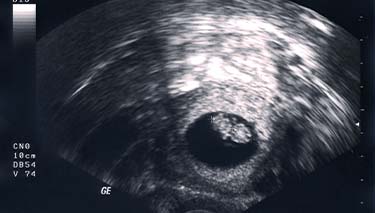

8 Week Ultrasound

An 8 week ultrasound can be both exciting and a bit scary. If this is your first ultrasound, you ll be understandably anxious. Getting a glimpse of your baby for the first time will be a memorable moment.

If you're not sure when you conceived, or, have had a previous miscarriage or pregnancy complications, an 8 10 week scan may be recommended. There's a lot which can be seen at 8 weeks gestation, including the baby's heartbeat and early development. It will also be possible to work out the baby's due date, which is why an 8 week ultrasound is often called a dating scan.

Most commonly an 8 week scan is done vaginally. A lubricated probe is inserted into the vagina and an image seen on a screen. Sonographers always seek consent for the procedure to be done and ask if the woman prefers she insert the probe herself or, if she's comfortable for the sonographer to do this. You ll need to have a full bladder. Another option is for a transabdominal ultrasound however, at 8 weeks pregnant it can be difficult to see very much through the abdominal wall.

The sonographer will talk with you about what they're looking for and what they can see. There will be times when they won t say much and instead, be concentrating on what they're doing. They ll be typing into a keyboard at the same time as looking at the screen. Specifically, they ll be taking measurements, checking for growth markers and doing a comprehensive check on the baby's development, as well as where it has implanted in your uterus.

At eight weeks pregnant, your baby will measure about 1.2 from the top of its head to its little tail. At an 8 week scan, it's possible to see the embryo's development, especially their big head and small body.